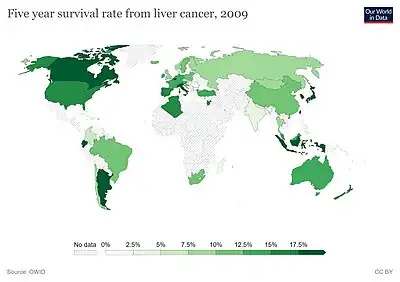

The vast majority of HCC cases and the lowest survival rates after treatment occur in Asia and sub-Saharan Africa, in countries where hepatitis B infection is endemic and many are infected from birth. The incidence of HCC in the United States and other developing countries is increasing due to an increase in hepatitis C virus infections. It is more than four times as common in males as in females, for unknown reasons.[4]

Prognosis

The usual outcome is poor because only 10–20% of hepatocellular carcinomas can be removed completely using surgery. If the cancer cannot be completely removed, the disease is usually deadly within 3 to 6 months.[80] This is partially due to late presentation with tumors, but also the lack of medical expertise and facilities in the regions with high HCC prevalence. However, survival can vary, and occasionally people survive much longer than 6 months. The prognosis for metastatic or unresectable HCC has improved due to the approval of Sorafenib (Nexavar®) for advanced HCC.

Epidemiology

HCC is one of the most common tumors worldwide. The epidemiology of HCC exhibits two main patterns, one in North America and Western Europe and another in non-Western countries, such as those in sub-Saharan Africa, Central and Southeast Asia, and the Amazon basin. Males are affected more than females usually, and it is most common between the ages of 30 and 50.[83]

Hepatocellular carcinoma causes 662,000 deaths worldwide per year[84] about half of them in China.

Africa and Asia

In some parts of the world, such as sub-Saharan Africa and Southeast Asia, HCC is the most common cancer, generally affecting men more than women, and with an age of onset between the late teens and 30s.[16] This variability is in part due to the different patterns of hepatitis B and hepatitis C transmission in different populations – infection at or around birth predispose to earlier cancers than if people are infected later. The time between hepatitis B infection and development into HCC can be years, even decades, but from diagnosis of HCC to death, the average survival period is only 5.9 months according to one Chinese study during the 1970-80s, or 3 months (median survival time) in sub-Saharan Africa according to Manson's textbook of tropical diseases. HCC is one of the deadliest cancers in China, where chronic hepatitis B is found in 90% of cases. In Japan, chronic hepatitis C is associated with 90% of HCC cases. Foods infected with Aspergillus flavus (especially peanuts and corns stored during prolonged wet seasons) which produces aflatoxins pose another risk factor for HCC.

North America and Western Europe

The most common malignant tumors in the liver represent metastases (spread) from tumors which originate elsewhere in the body.[83] Among cancers that originate from liver tissue, HCC is the most common primary liver cancer. In the United States, the US surveillance, epidemiology, and end results database program, shows that HCC accounts for 65% of all cases of liver cancers.[85] As screening programs are in place for high-risk persons with chronic liver disease, HCC is often discovered much earlier in Western countries than in developing regions such as sub-Saharan Africa.

The incidence of HCC is relatively lower in the Western Hemisphere than in Eastern Asia. However, despite the statistics being low, the diagnosis of HCC has increased since the 1980s and it is continuing to increase, making it one of the rising causes of death due to cancer. The common risk factor for HCC is hepatitis C, along with other health issues.[86][87]